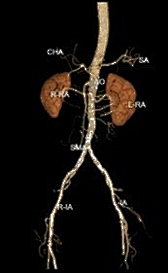

术前CTA:腹主及双侧髂动脉多处钙化病变伴管腔狭窄。

★ 造影评估

经腹主动脉造影如术中所见双侧髂动脉中-重度狭窄。

★ 术后造影

左右髂外动脉狭窄明显好转

★ 术后CTA

显示钙化病变重塑,双侧髂动脉管腔较前明显改善